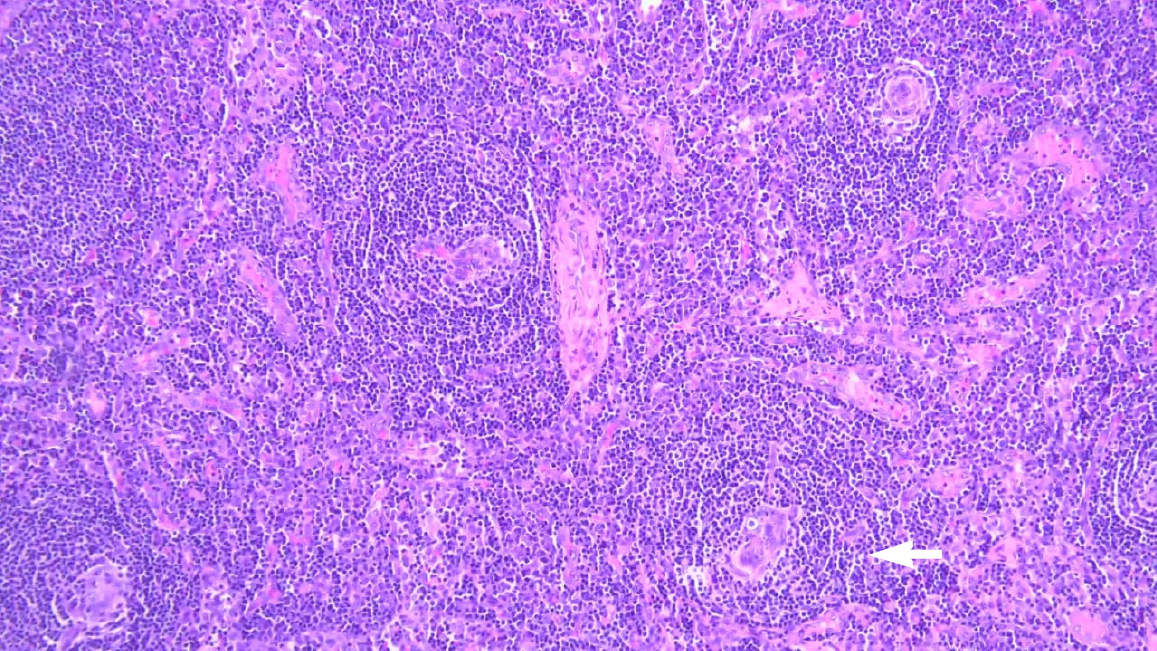

Figure 2 Hematoxylin and eosin-stained lymph node biopsy with atretic germinal centres.

Mantle zones thickened with lymphocytes arranged in layers give an onion skin appearance (white arrow).